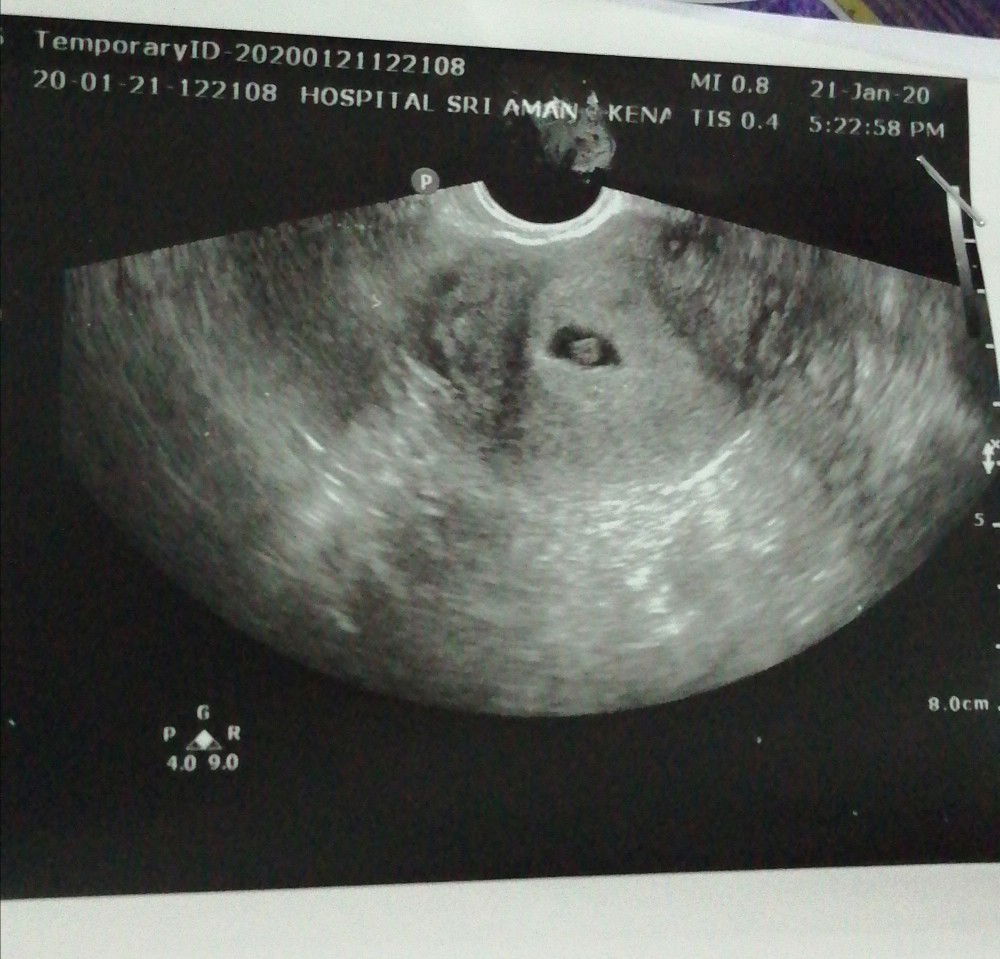

Kandungan sy bru masuk 9w.. Bbrpa hr ne ada kluar darah sikit2. Tdi pegi kk dr kk scan nampak kantung saja.. Cek kat bawah dr kata sy kemungkinan miscarriage sbb darah memang kluar dr dalam ?.. Trus refer pegi hosp. Dr kat hosp scan dr bwah nampak kantung dn baby kecik saja size.. Samar2 saja nampak, macam jadi macam tidak kata dr.. Kena tunggu 2w kena scan lagi.. Klau size baby tak da perubahan still kecik dr kata kena cuci ?